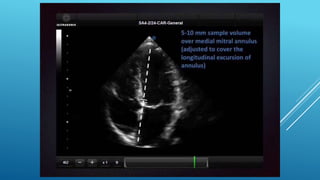

โ€ข Tricuspid annular plane systolic excursion

โ€ข TAPSE of <17 mm indicates RV dysfunction

โ€ข Tricuspid annular systolic velocity

โ€ข Tissue Doppler of the free lateral wall

โ€ข An Sโ€™ value < 9.5 cm/s should raise the suspicion for abnormal RV function